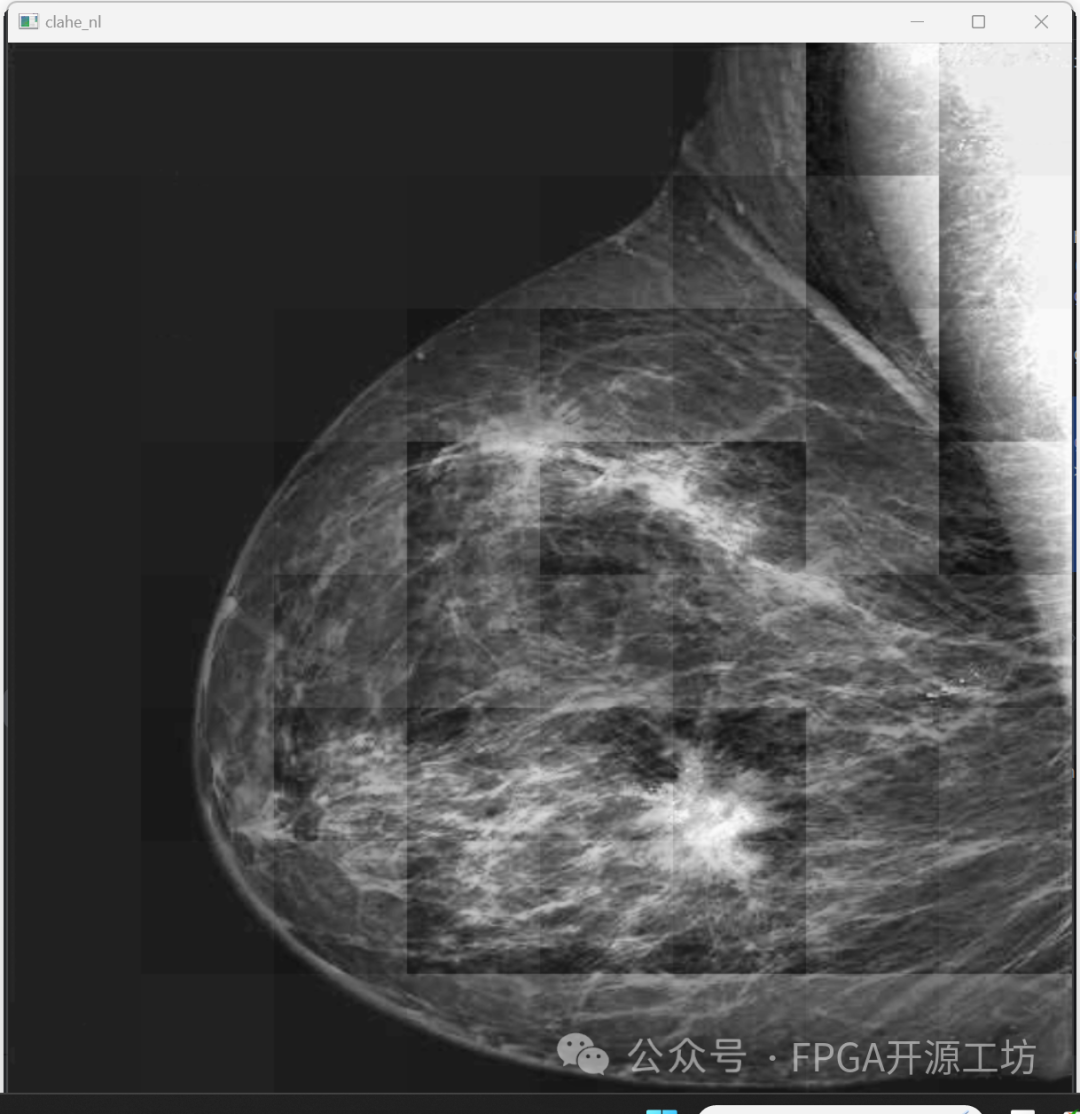

来看一下最后的效果:

87c54c5a-ab7f-11ee-8b88-92fbcf53809c.png

可以看到相对于没有进行限制对比度的效果要好很多。

下面这幅图是没有限制对比度阈值的结果:

87dda7a0-ab7f-11ee-8b88-92fbcf53809c.png